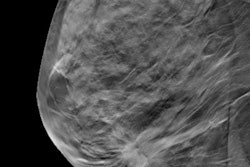

The money, funded by HHS's Health Resources and Services Administration (HSRA), aims to promote access to cervical, breast, and colorectal cancer screenings at HSRA-funded community health centers. Grant applications must be submitted through the grants.gov website by June 15.